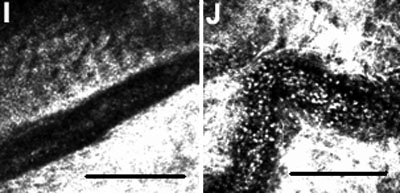

Heidelberg Retina Tomograph II in vivo confocal microscopy images of conjunctival epithelium (A, C, and E) and substantia propria (B, D, and F) 4 h after injections of BSS (A and B), LPS (C and D), and LPS+anti-TNF-α (E and F; 400x400 μm). C: The dendritic-shaped cells (arrows) were surrounded by many smaller round cells suggestive of lymphocytes (arrowheads). Cell counts of inflammatory cell infiltration in the epithelium/mm2 (G) and substantia propria/mm2 (H). The asterisk indicates a p<0.001 compared to BSS-injected conjunctivas and the sharp (hash mark) denotes a p<0.01 compared to LPS+anti-TNF-α-injected conjunctivas. Images of a blood vessel in a BSS-injected conjunctiva I and in a LPS-injected conjunctiva (J) show in vivo rolling and leukocyte migration of inflammatory cells. The scale bar indicates 100 μm.